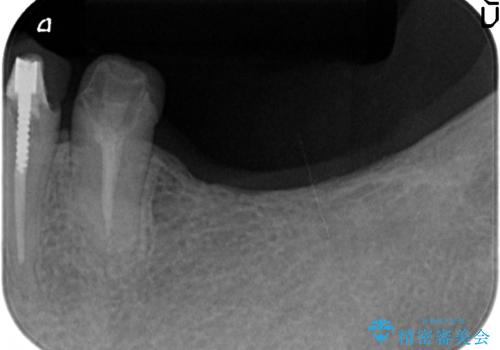

ここの歯の状態を精密に検査し、根管治療、セラミック治療、インプラント治療を含む総合的な歯科治療を計画します。

- 242万円(ジルコニアクラウン・仮歯×7本 インプラント×2本)費用は治療当時の料金となります